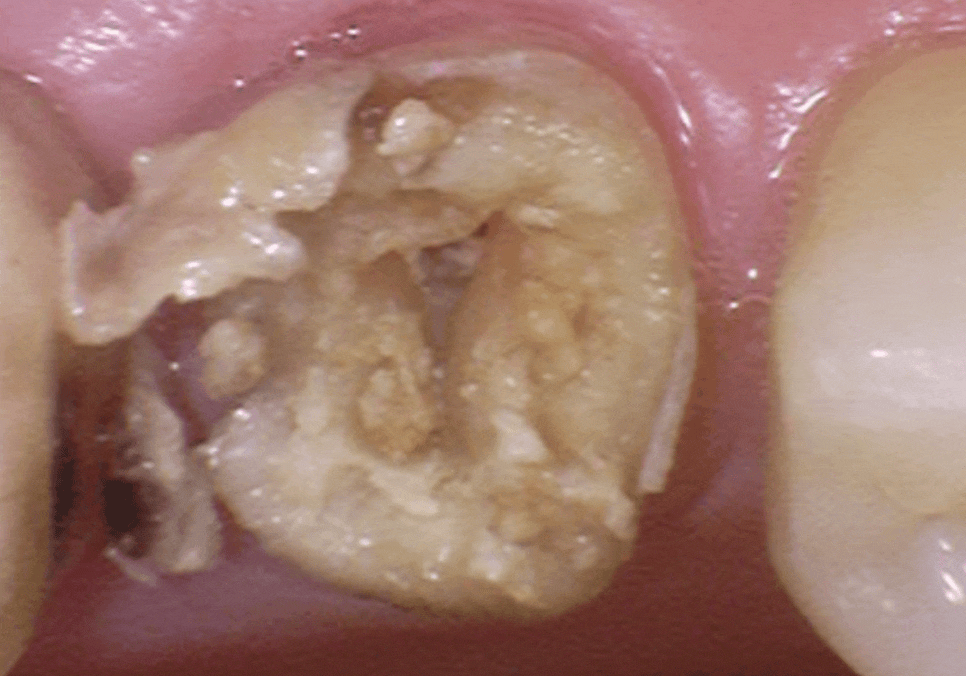

240812

충치가 있긴 했지만

치아 뿌리는 튼튼했기에,

치아 내부의 오염된 신경관을

청소하는 신경치료를 진행했습니다.

251010

오염된 신경을 4번에 걸쳐

꼼꼼히 제거하고 소독한 뒤,

이번에는 구멍이 잘 나지 않는

단단한 재료인 '지르코니아'로 씌워,

튼튼하게 마무리해 드렸습니다.

251103